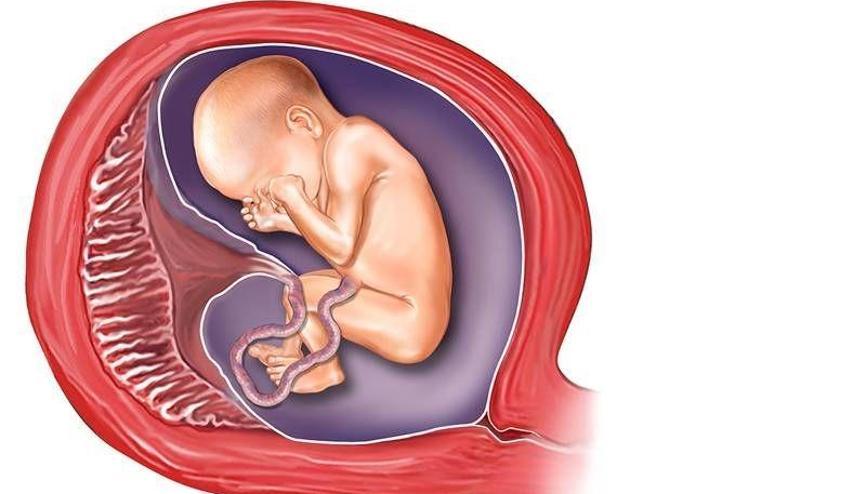

Многоводие при беременности: симптомы и лечение